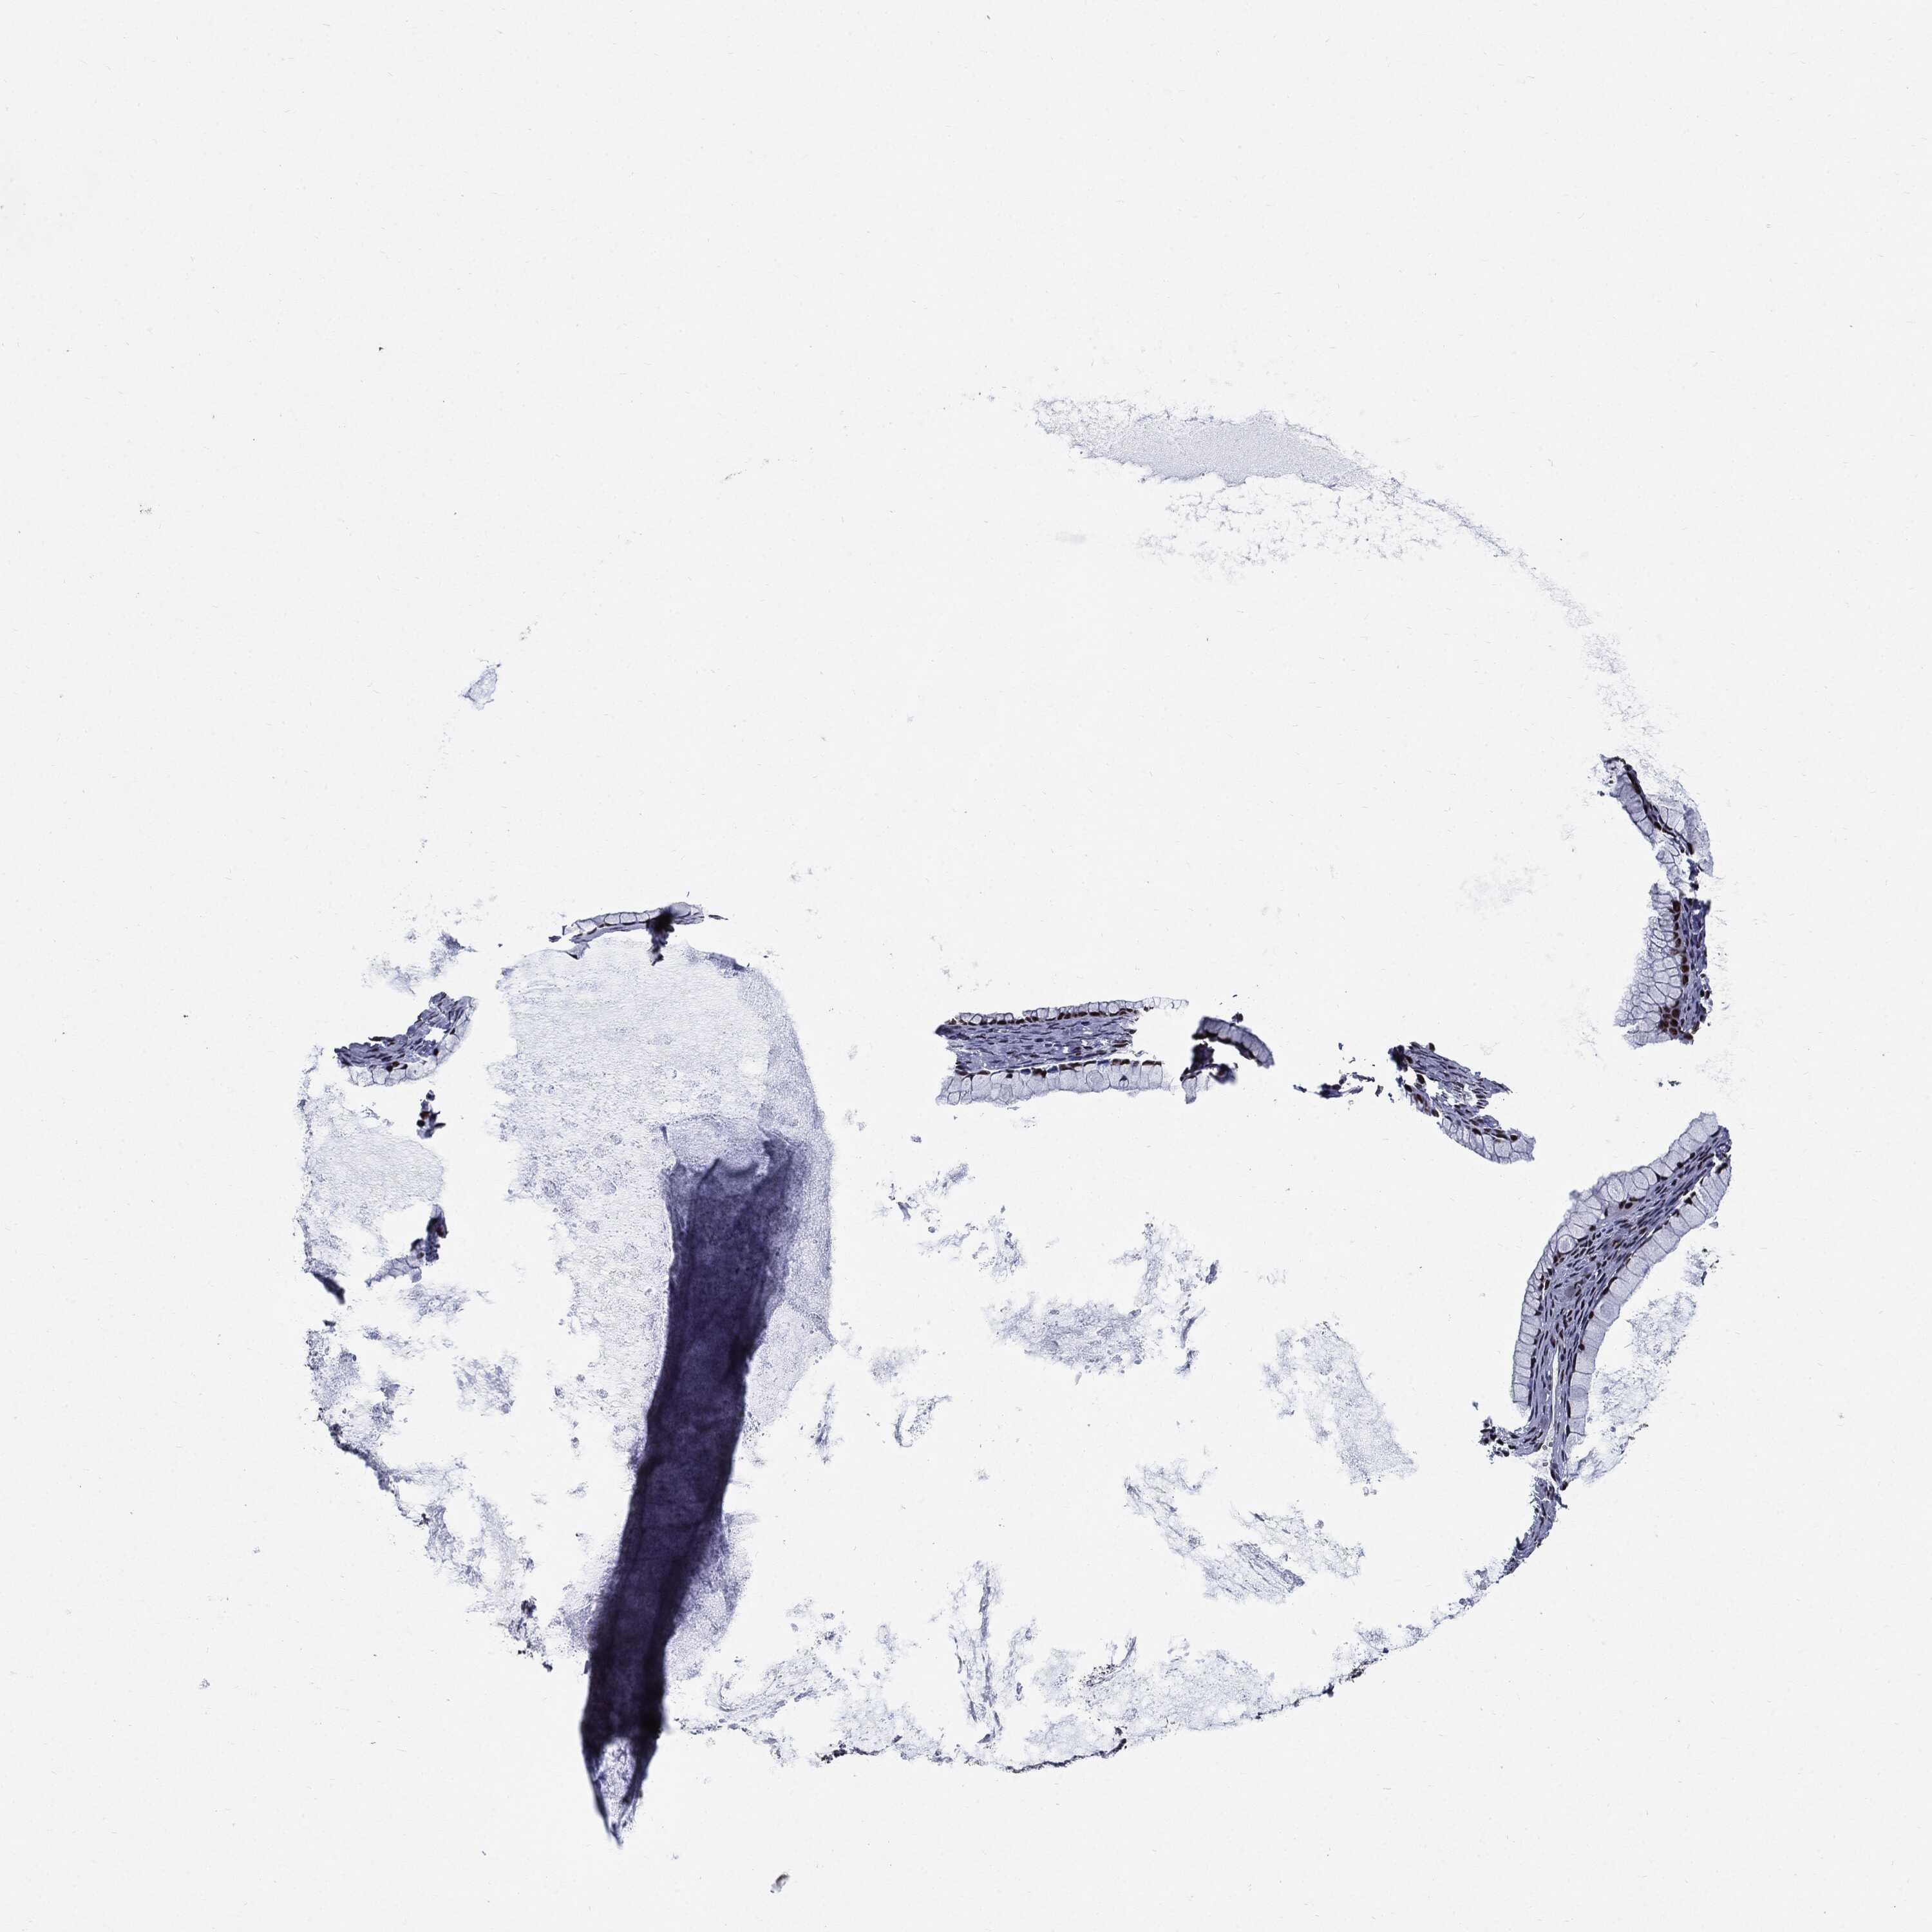

OVARIAN CANCER - Protein expressioni

A mouse-over function shows sample information and annotation data. Click on an image to view it in a full screen mode. Samples can be filtered based on level of antibody staining by selecting one or several of the following categories: high, medium, low and not detected. The assay and annotation is described here.

Note that samples used for immunohistochemistry by the Human Protein Atlas do not correspond to samples in the TCGA dataset.

Antibody stainingi

Antibody staining in the annotated cell types in the current human tissue is reported as not detected, low, medium, or high, based on conventional immunohistochemistry profiling in selected tissues. This score is based on the combination of the staining intensity and fraction of stained cells.

Each image is clickable and will lead to virtual microscopy that enables deeper exploration of all samples and also displays staining intensity scores, fraction scores and subcellular localization as well as patient and tissue information for each sample.

Antibody HPA024037

Antibody HPA065325

Antibody HPA074591

Antibody CAB025417

Staining

High

Medium

Low

Not detected

Intensity

Strong

Moderate

Weak

Negative

Quantity

>75%

75%-25%

<25%

None

Location

Nuclear

Cytoplasmic/membranous

Cytoplasmic/membranous,nuclear

Cystadenocarcinoma, serous, NOS

Carcinoma, endometroid

Cystadenocarcinoma, mucinous, NOS

Carcinoma, NOS